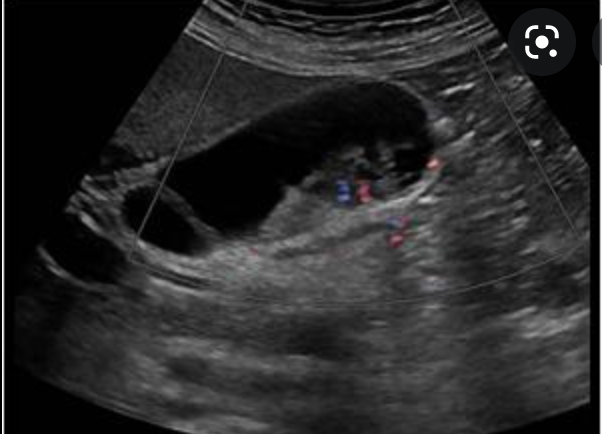

What is this?

Adenomyomatosis

- most comon form of hyperplastic cholesterolosis

- marked hyperplasia of the GB wall

- Epithelium herniates into the wall

- forms rokitansky-Aschoff sinuses

- May be focal or diffuse

- IMAGING FINDINGS

- Rokitansky-Ashkoff sinues

- hypoechoic if contain bile

- hyperechoic if contain sludge or calculi

- High amplitude foic in the wall (cholesterol crystals) that produce comet tail artifacts (V shpaed ring down artifacts)

- Thickening of GB wall is common but non specific

- inflammation is not typical

- hypercontractility